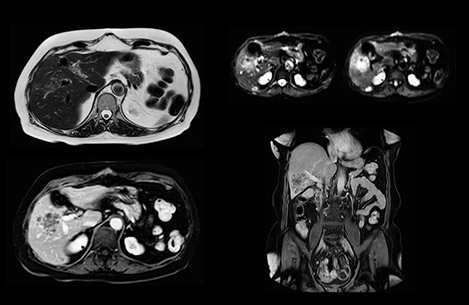

In this example the image quality of the MultiVane XD images is evidently better than in the images without MultiVane XD. Ingenia 1.5T with dS Torso coil solution.

Dr. Baumann then implemented MultiVane XD for motion correction. It uses an extended reconstruction algorithm for imaging that is virtually motion free. “With MultiVane XD we get excellent motion-corrected images with high spatial resolution. We typically first optimize our scan for high image quality, and when satisfied with that, we try to reduce the scan time. So, we combined MultiVane XD with dS SENSE, which allows us to shorten the scan time,” he explains. “The performance of MultiVane XD in liver imaging is outstanding. MultiVane XD with dS SENSE is a powerful development in improving liver image quality.” “As we use breathhold imaging for T2-weighted liver scans, we depend on the patient’s ability to cooperate with the exam. This can present a real challenge when we are looking for small lesions, such as in our oncological patients. However, with MultiVane XD motion correction, we get excellent images. This is important for our surgeons, because they want to know exactly where the lesions are.”

“Our liver exams are quite fast,” says Dr. Baumann. “If the patient tolerates it, we use an arms-up position to reduce the FOV and speed up the exam with dS SENSE.” “We acquire one transversal high resolution T2-weighted sequence with 3 mm slice thickness, for example for pancreas or liver lesions. Then we also add a T2 fat suppressed MultiVane XD SPIR sequence. We perform these two routinely in our liver imaging. We use high dS SENSE factors to significantly shorten scan times to 2-4 minutes, which can improve our protocol; it’s a very robust scan.” “We include mDIXON for the dynamic sequences because of the robust and homogeneous fat suppression we get with that. We had been using eTHRIVE, but we are now quite happy with mDIXON. Sometimes we use a medication to calm the bowels, to further improve the image quality.”